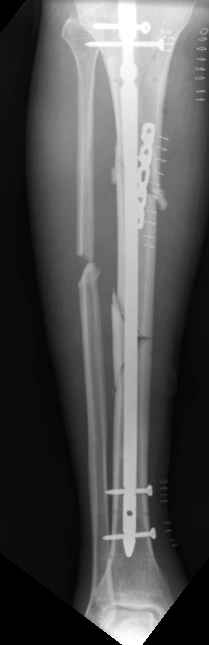

Enes Kanlic 18 Декабрь 2003, 10:08

1

2

3

4

5

6

I agree with Dr. Wilson,

1. Nailing proximal tibias: Starting point has to be high (still not to

penetrate knee capsule) and a little bit lateral from midpoint. Blocking

screws are very helpful and sometimes necessary, see attached Slides 1 and

2).

2. Plate could be used, just needs to be done right (minimally invasive,

preservation of soft tissues, slides 4 and 5)

3. If it is impossible to get reduction trying to pass the nail distally,

plate could be added (as on slides 5 and 6).

In this particular patient, if soft tissues are good, I would:

A) Exchange (closed method) the nail (shorter one, starting point a little

bit more lateral) and blocking screws probably would be needed, and if that

does not work

B) I would open the fracture, would help my reduction with forceps or plate

and still nail it.